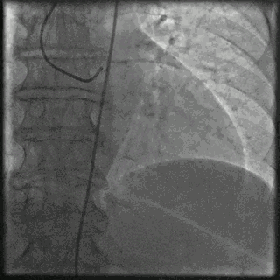

La coronarographie est l'examen de référence pour le diagnostic de la maladie coronarienne, elle est sûrement précise, mais son inconvénient est qu'elle est invasive, qu'elle nécessite une hospitalisation dans le laboratoire de cathétérisme et que si la sténose de l'artère principale est supérieure à 75 %, la pose d'un stent peut être envisagée. La tomodensitométrie coronaire est un examen non invasif qui ne nécessite pas d'hospitalisation et peut être réalisé en ambulatoire, mais sa précision est médiocre et les problèmes doivent être clarifiés par une nouvelle imagerie.

Nous suggérons aux patients souffrant d'une maladie coronarienne de prendre de l'aspirine et des statines pendant une longue période afin de stabiliser la plaque et de prévenir la thrombose, tandis que les patients souffrant de maladies sous-jacentes telles que l'hypertension, le diabète sucré et l'hyperlipidémie devraient prêter attention au traitement des maladies sous-jacentes et contrôler leur tension artérielle, leur glycémie et leur taux de lipides sanguins selon les normes en vigueur. Pour les patients présentant une sténose coronaire de plus de 75 % ou des crises d'angine de poitrine fréquentes ou un infarctus aigu du myocarde, l'intervention par endoprothèse est réalisable. Pour les patients présentant des lésions coronariennes complexes ou d'autres maladies sous-jacentes, un traitement complémentaire, tel qu'un pontage chirurgical, peut être réalisé sous la supervision des médecins.

Une fois la maladie coronarienne diagnostiquée, il convient de veiller à l'utilisation à long terme de l'aspirine et des statines dans la vie quotidienne, et la nitroglycérine doit toujours être disponible pour les personnes souffrant de crises d'angine de poitrine. Pour les patients souffrant de crises d'angine fréquentes, d'une sténose coronaire de plus de 75 % ou d'un infarctus aigu du myocarde, l'intervention d'un stent peut être envisagée. Pour les patients souffrant d'une pathologie complexe, un pontage est possible si nécessaire. Tout en standardisant le traitement, nous devrions également veiller à surveiller les changements de l'état de santé et à procéder à des examens réguliers.

En outre, certains patients présentant une sténose sévère, si les médicaments sont inefficaces, ou des patients souffrant d'un infarctus du myocarde aigu peuvent nécessiter l'implantation d'une endoprothèse cardiaque. Les lésions sévères à trois branches et les lésions du tronc principal gauche peuvent nécessiter un pontage cardiaque chirurgical.